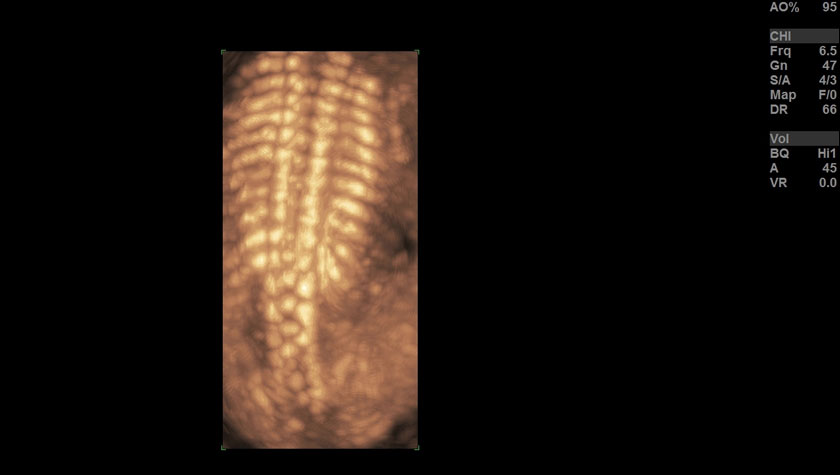

Позвоночник плода в 3D, датчик RAB6-D